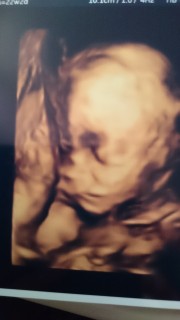

健診に通っている大学病院では、4Dエコーちらっと見せてくれるだけ。動画が欲しくて、録ってくれる病院を探して行って来ました!撮影のみ。との話でしたが、性別を見てくれました。旦那と二人でシンボル確認!男の子決定でーす。右手で鼻辺りを隠してましたが、旦那似な気がします。もう少しすると、お肉がついてぷくぷくの赤ちゃんらしい顔つきになるよーと言われました。楽しみ!念願のカラー動画、写真嬉しいです